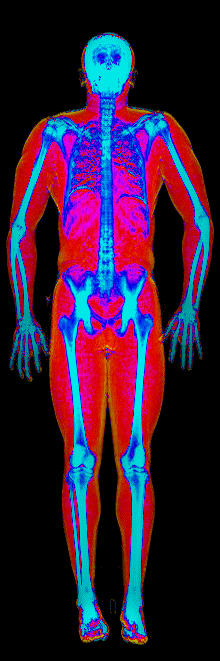

What Muscle Gain Looks Like on a DEXA Scan

Gained 12.0 lb lean, lost 24.9 lb fat · 183 → 170 lb · Age 37

Gained 10.0 lb lean · 140 → 152 lb · Age 23